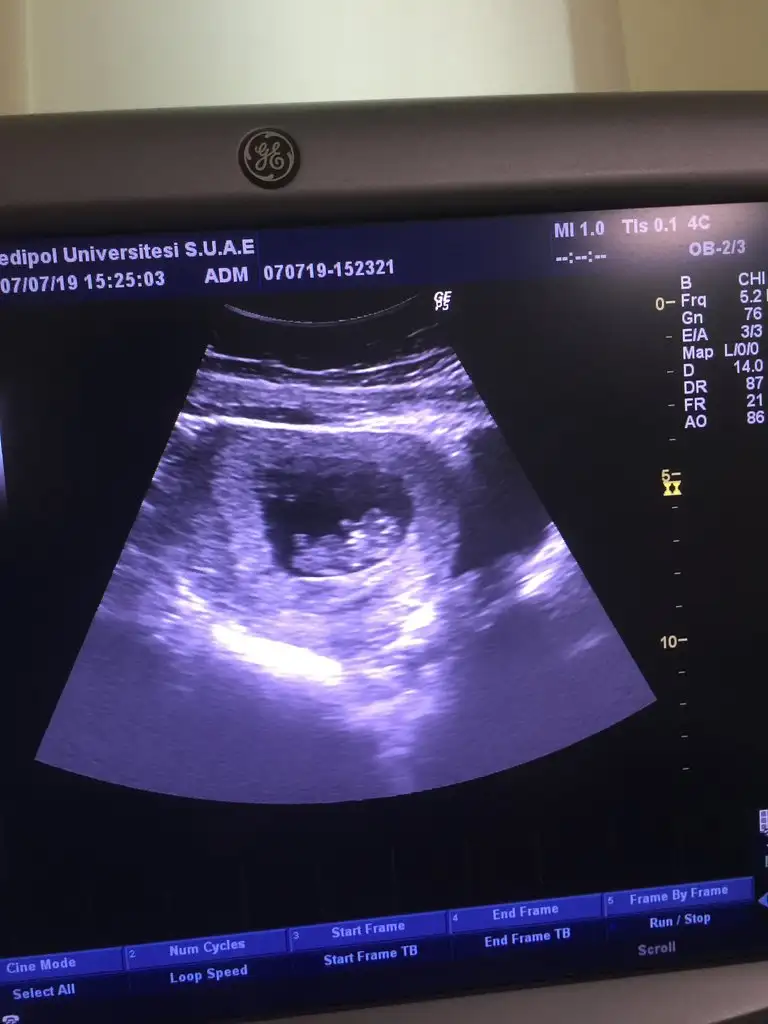

Burda bi başlıkta görüp incelemiştim ben de, nub teorisi diye bişi, kız ve erkek genital organı oluşmadan önce ikisi de çıkıntı şeklinde oluyomuş, bu çıkıntıya nub diyoruz, erkek bebekse bu nub daha dik açıyla, kız bebekse 30°lik açıyla duruyomuş, bu ultrasonda da doğru gördüysem bebiş ayaklarını baya kaldırmış, düz gibi düşününce ordaki beyazlığı dik diye düşündüm ben de. Ama hiiiç anlamam, öyle okuduğum bi kaç şeyden yorum yaptım işte 🤣

Kız orda nub nerde görüyonuz ayaklarının ikiside yukarda ortası boş gibi duruo 😀😀😀 ay allah hepimize hayırlısı ve sağlıklısını versin ama tabi gönlümden geçen kız😍😍

Yaaaa o zaman bende nub yorumu istiyorum 😌😌 çok uzaktan almış dr görüntüyü